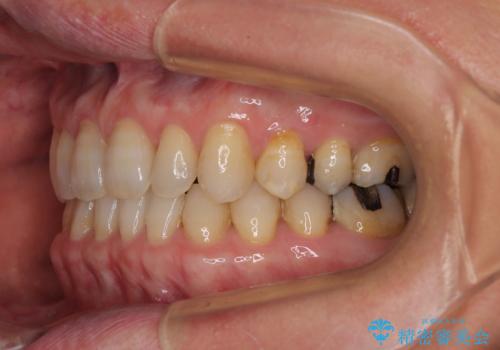

- 前歯のデコボコと隙間の空いた歯列を気にして来院された患者様です。

下顎前歯が隠れるほどのディープバイトにより、強い咬合力と突き上げで上顎歯列に隙間が空いている状態でした。

手前に傾斜している奥歯をワイヤー装置で立ち上がらせ、咬み合わせの高さを挙上することで突き上げを解消し、空隙歯列を改善していくこととしました。

ディープバイトが改善され、睡眠時の食いしばりも緩和され、顎への負担が軽減されました。